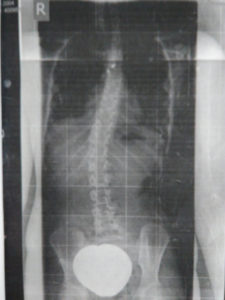

Durch jahrzehntelanger Erfahrung in der Behandlung von Wirbelsäulen können wir die Herstellung von fixierenden und stabilisierenden sowie wachstumslenkenden Rumpforthesen nach modernsten Kriterien gewährleisten.

Rumpforthesen werden eingesetzt, um die Wirbelsäule zu fixieren, zu korrigieren (Redression), aufzurichten (Reklination), zu entdrehen (Derotation) oder zu strecken (Extension). Unterschieden werden passive und aktive Rumpforthesen. Die passiven Rumpforthesen, auch Stützkorsetts genannt, werden zur Entlastung instabiler Wirbelsäulen eingesetzt, u.a. mit dem Ziel der Schmerzlinderung. Aktive Rumpforthesen sollen Fehlstellungen der Wirbelsäule korrigieren, wie sie bspw. als Folge von Erkrankungen wie Skoliose, Kyphose, Morbus Scheuermann, Hyperlordose und Osteoporose auftreten. Rumpforthesen werden bei Kindern und Jugendlichen eingesetzt, um das Wachstum zu lenken und Fehlstellungen zu korrigieren.